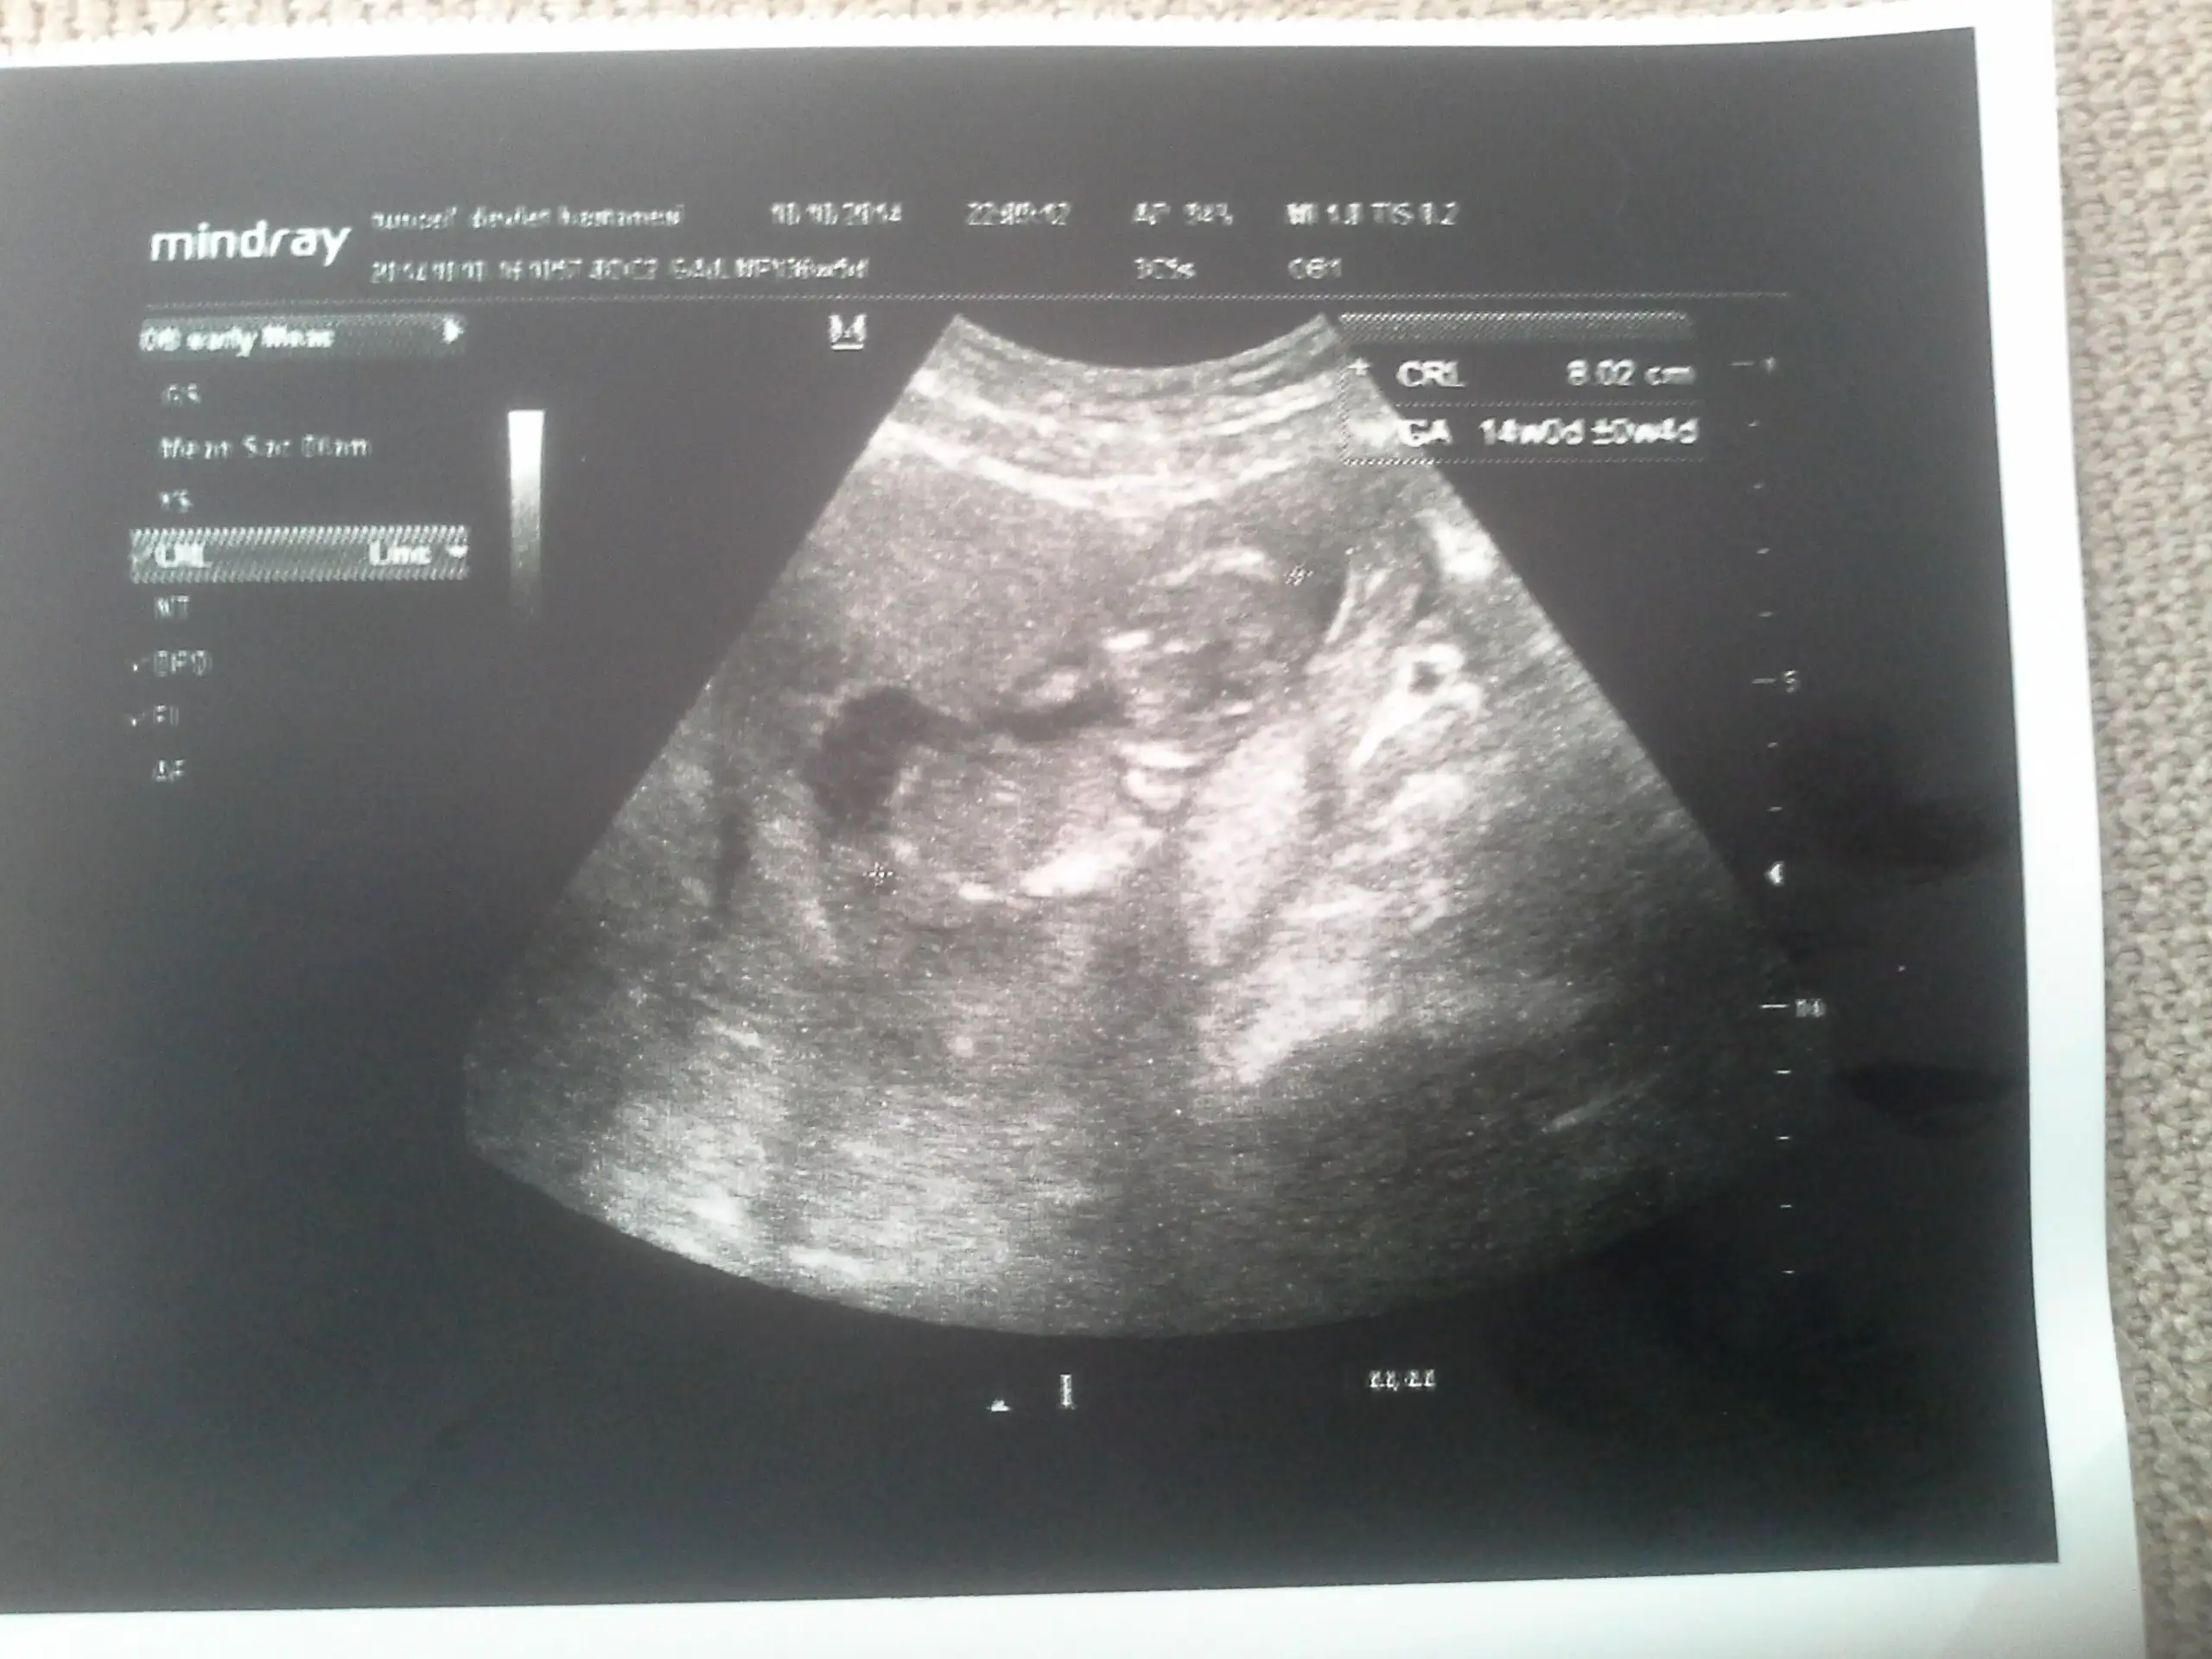

Canim yukari dogru bakan biaey var ama tam olarak nub mu gobek bagimi cozemedim bacaklariyla kapamis gibj:)Eki Görüntüle 1279243 Eki Görüntüle 1279245 Arkadaslar burda 12+5 gunluguz cok merak ediyorum tahmin de bulunabilirmisiz